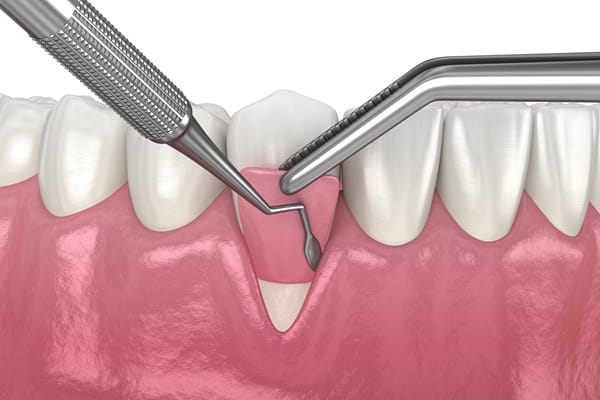

Tooth Extractions

A tooth extraction is a common dental procedure where a tooth is carefully removed from its socket within the jawbone. This might be necessary for various reasons, all aimed at protecting your overall oral health and preventing further complications that could affect adjacent teeth or your general well-being.